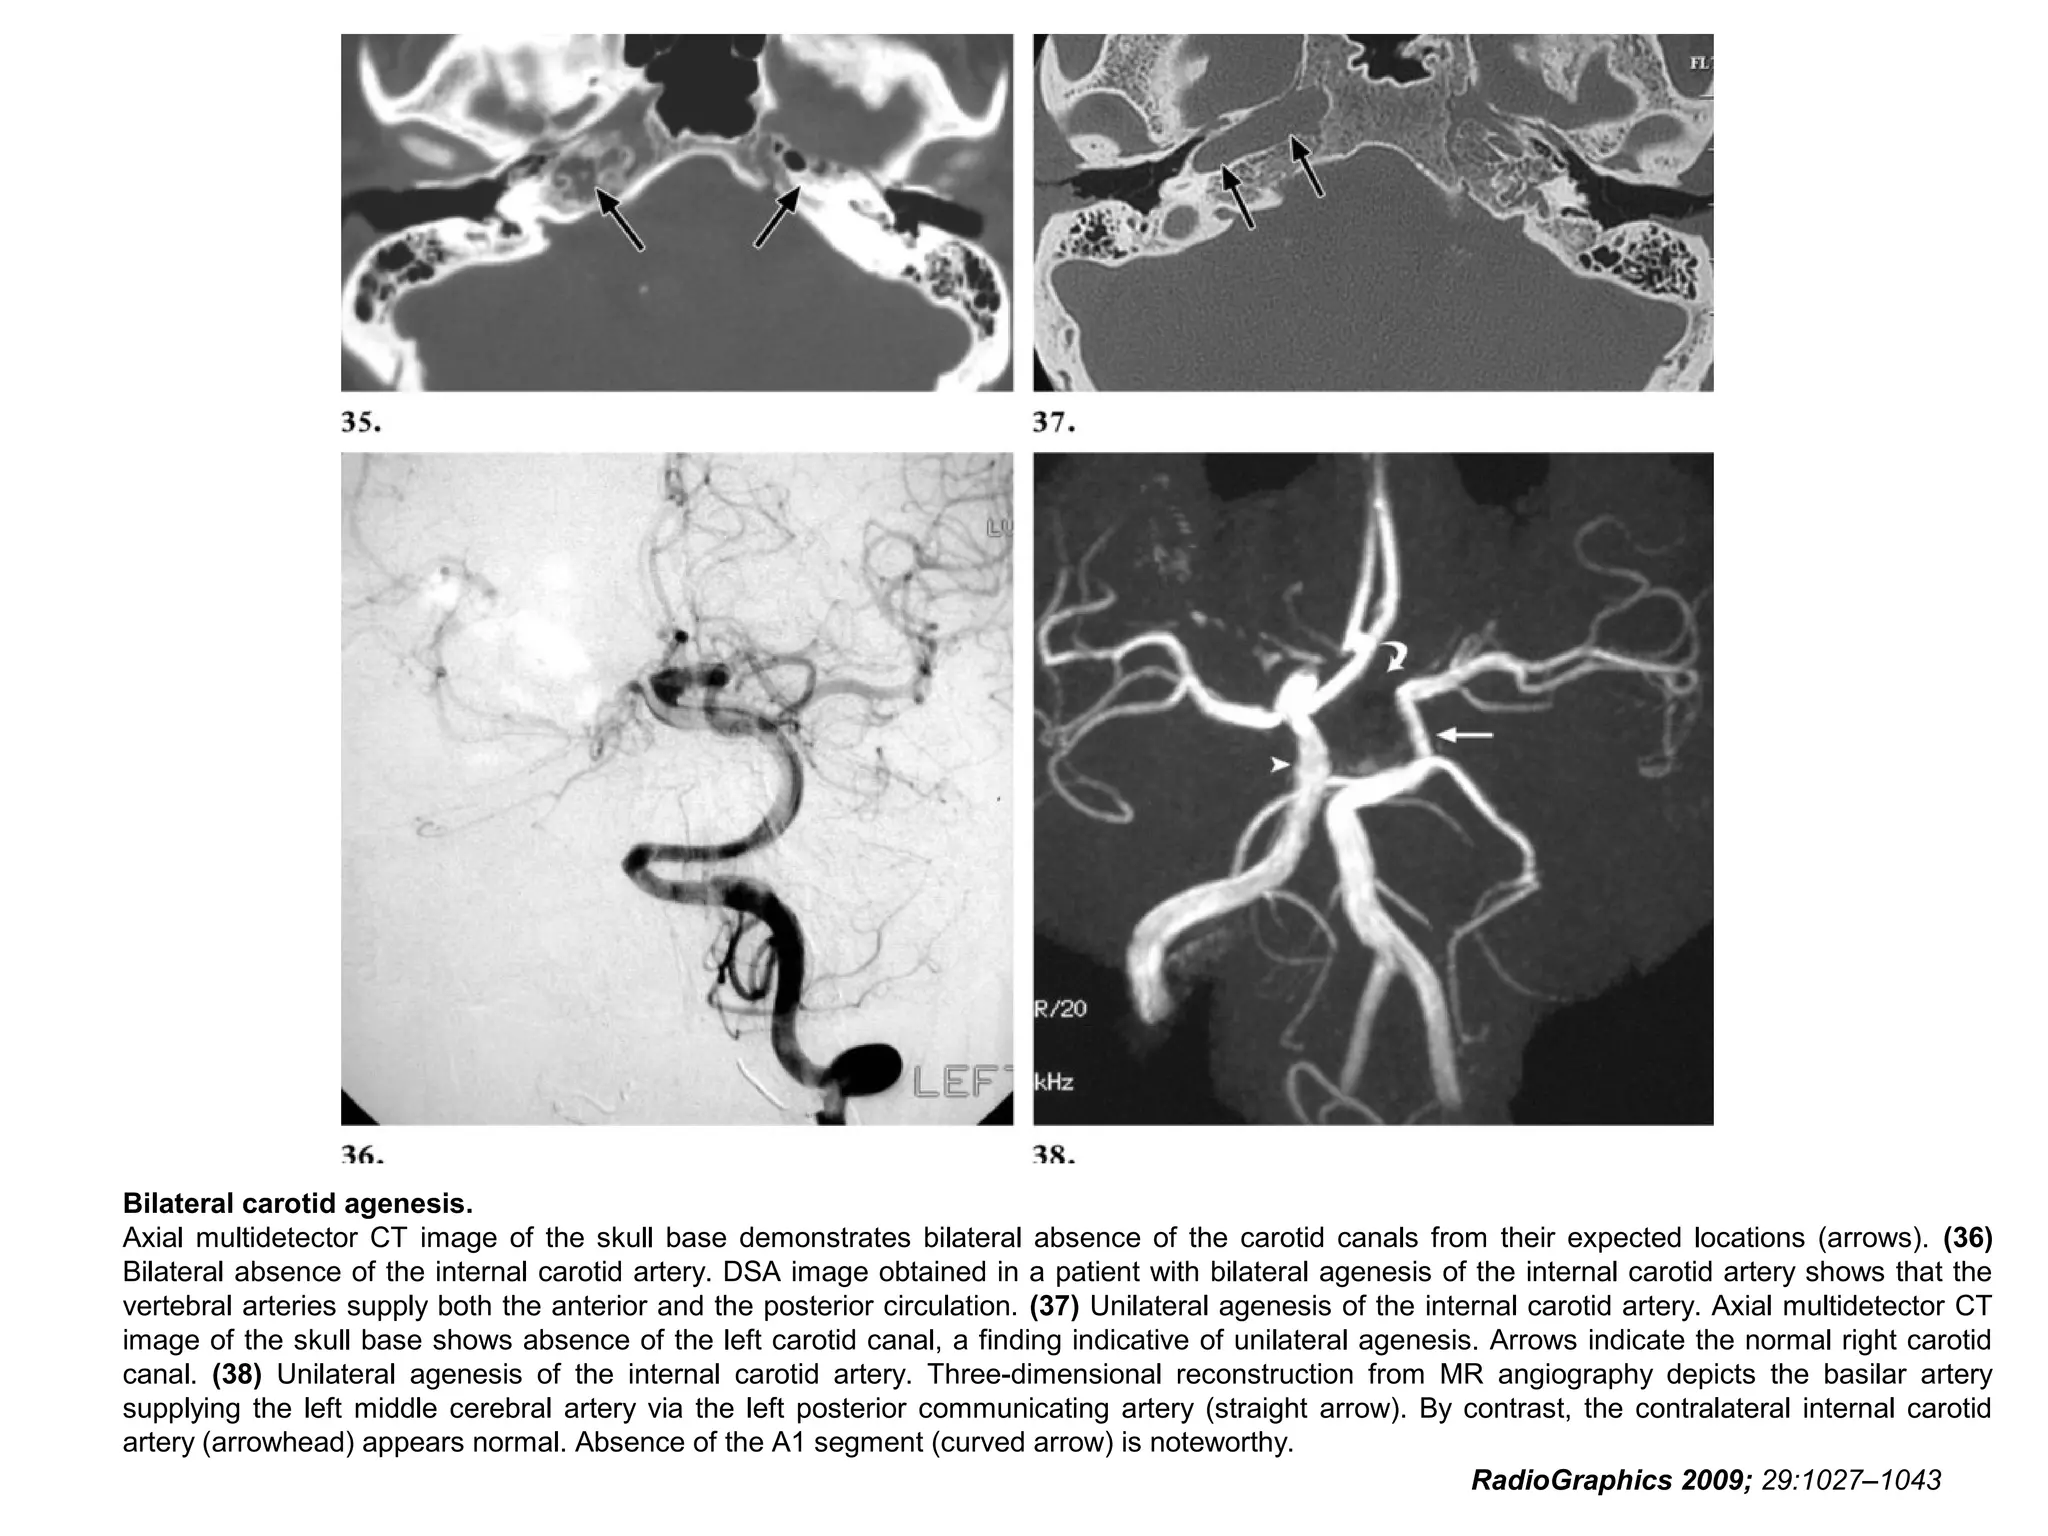

Internal Carotid Artery Agenesis

• Congenital absence of the internal carotid artery has a

prevalence of 0.01%.

• CT of the skull base and CT angiography in such cases

demonstrate an absence of the carotid canal.

• The anomaly may be unilateral or, more rarely, bilateral.

• The recognition of internal carotid artery agenesis is

important, especially in patients with cerebral

thromboembolic disease due to atherosclerosis of the

vertebrobasilar system.

• Poor collateral blood supply to the head places these

individuals at high risk during conventional angiography

and surgery.

• There is also a strong association between internal

carotid artery agenesis and the development of

intracranial aneurysms.

RadioGraphics 2009; 29:1027–1043

Bilateral carotid agenesis.

Axial multidetector CT image of the skull base demonstrates bilateral absence of the carotid canals from their expected locations (arrows). (36)

Bilateral absence of the internal carotid artery. DSA image obtained in a patient with bilateral agenesis of the internal carotid artery shows that the

vertebral arteries supply both the anterior and the posterior circulation. (37) Unilateral agenesis of the internal carotid artery. Axial multidetector CT

image of the skull base shows absence of the left carotid canal, a finding indicative of unilateral agenesis. Arrows indicate the normal right carotid

canal. (38) Unilateral agenesis of the internal carotid artery. Three-dimensional reconstruction from MR angiography depicts the basilar artery

supplying the left middle cerebral artery via the left posterior communicating artery (straight arrow). By contrast, the contralateral internal carotid

artery (arrowhead) appears normal. Absence of the A1 segment (curved arrow) is noteworthy.

Normal internal carotid arteries are not seen in the carotid

spaces, and no carotid canals are noted on the high

resolution CT scan of the skull base.

The middle cerebral artery arises from the basilar artery

through an enlarged posterior communicating artery.

Images from www.sherlockradiogy.com

Internal Carotid ArteryAgenesis • Congenital absence of the internal carotid artery has a prevalence of 0.01%. • CT of the skull base and CT angiography in such cases demonstrate an absence of the carotid canal. • The anomaly may be unilateral or, more rarely, bilateral. • The recognition of internal carotid artery agenesis is important, especially in patients with cerebral thromboembolic disease due to atherosclerosis of the vertebrobasilar system. • Poor collateral blood supply to the head places these individuals at high risk during conventional angiography and surgery. • There is also a strong association between internal carotid artery agenesis and the development of intracranial aneurysms. RadioGraphics 2009; 29:1027–1043

• 95.

Bilateral carotid agenesis. Axialmultidetector CT image of the skull base demonstrates bilateral absence of the carotid canals from their expected locations (arrows). (36) Bilateral absence of the internal carotid artery. DSA image obtained in a patient with bilateral agenesis of the internal carotid artery shows that the vertebral arteries supply both the anterior and the posterior circulation. (37) Unilateral agenesis of the internal carotid artery. Axial multidetector CT image of the skull base shows absence of the left carotid canal, a finding indicative of unilateral agenesis. Arrows indicate the normal right carotid canal. (38) Unilateral agenesis of the internal carotid artery. Three-dimensional reconstruction from MR angiography depicts the basilar artery supplying the left middle cerebral artery via the left posterior communicating artery (straight arrow). By contrast, the contralateral internal carotid artery (arrowhead) appears normal. Absence of the A1 segment (curved arrow) is noteworthy. RadioGraphics 2009; 29:1027–1043

• 96.

Bilateral carotid agenesis. Normalinternal carotid arteries are not seen in the carotid spaces, and no carotid canals are noted on the high resolution CT scan of the skull base. The middle cerebral artery arises from the basilar artery through an enlarged posterior communicating artery. Images from www.sherlockradiogy.com